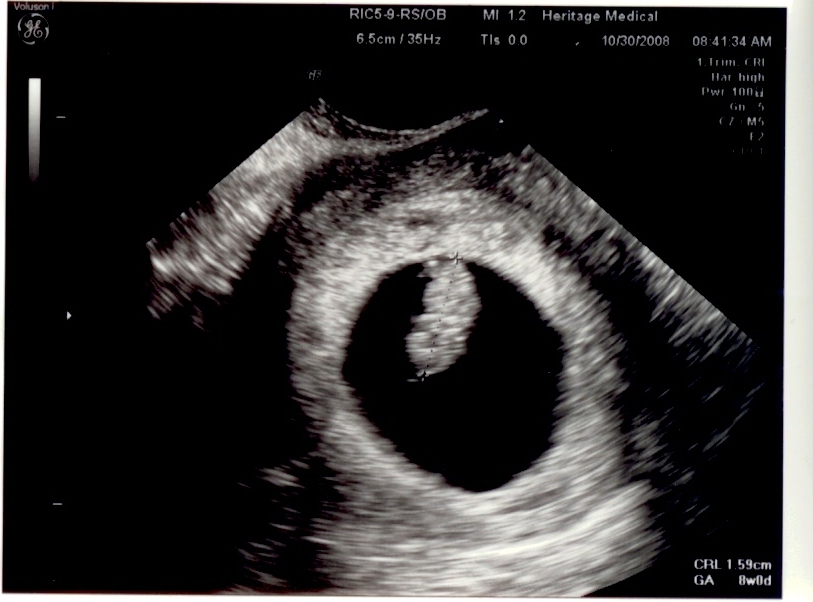

Joseph's Ultrasounds

12 Weeks